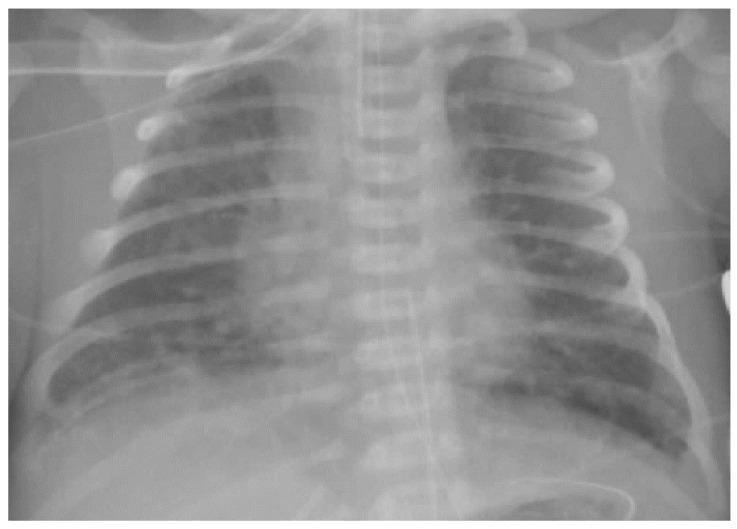

胎粪吸入综合征:一篇叙述性综述

Meconium Aspiration Syndrome: A Narrative Review.

Meconium aspiration syndrome is a clinical condition characterized by respiratory failure occurring in neonates born through meconium-stained amniotic fluid. Worldwide, the incidence has declined in developed countries thanks to improved obstetric practices and perinatal care while challenges persist in developing countries. Despite the improved survival rate over the last decades, long-term morbidity among survivors remains a major concern. Since the 1960s, relevant changes have occurred in the perinatal and postnatal management of such patients but the most appropriate approach is still a matter of debate. This review offers an updated overview of the epidemiology, etiopathogenesis, diagnosis, management and prognosis of infants with meconium aspiration syndrome.

摘要

胎粪吸入综合征是一种临床病症,其特征为出生于羊水被胎粪污染的新生儿出现呼吸衰竭。在全球范围内,由于产科实践和围产期护理的改善,发达国家的发病率有所下降,而发展中国家仍面临挑战。尽管在过去几十年中存活率有所提高,但幸存者的长期发病率仍是一个主要问题。自20世纪60年代以来,此类患者的围产期和产后管理发生了相关变化,但最合适的方法仍存在争议。本综述提供了胎粪吸入综合征患儿的流行病学、病因发病机制、诊断、管理和预后的最新概述。